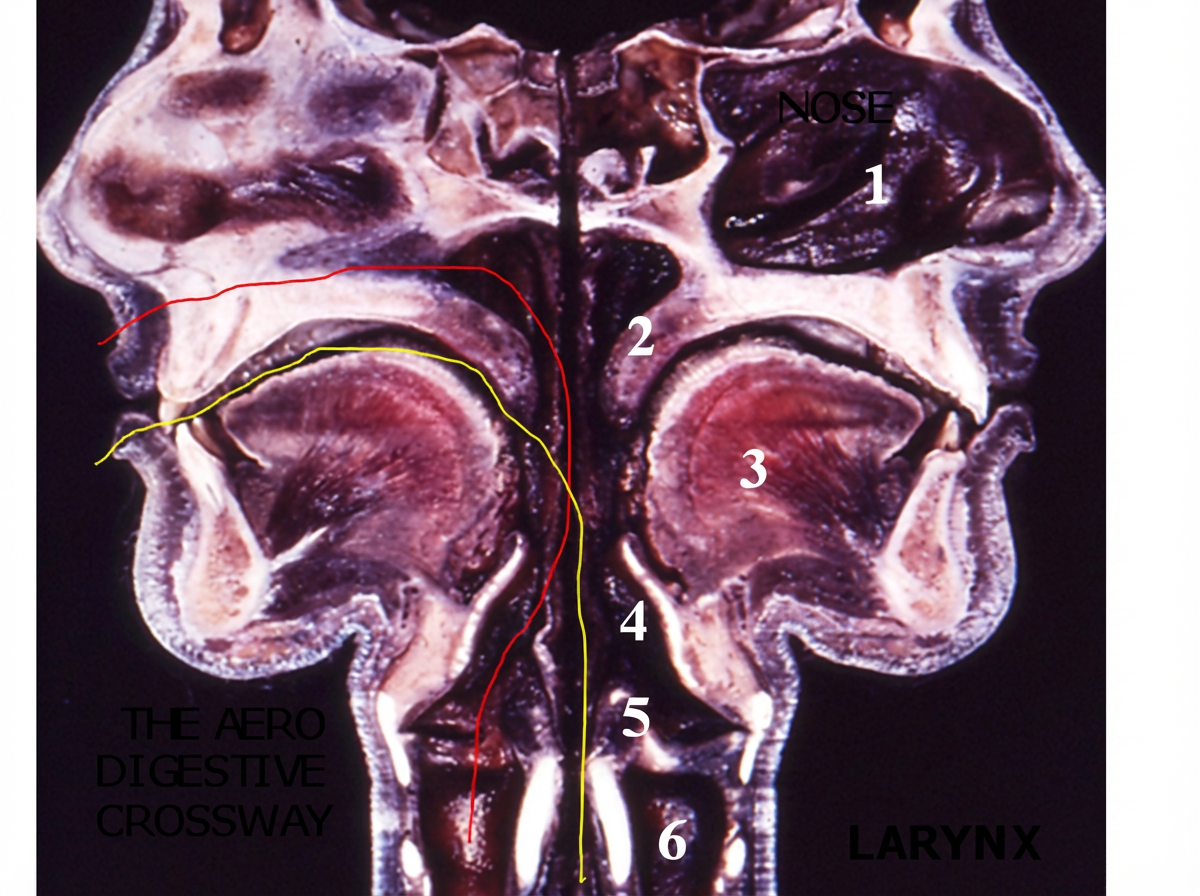

3. Le carrefour aéro-digestif (Fig. 3).

Deux conduits de nature différente se trouvent dans la partie viscérale de la face et du cou: l’un, aérien (en rouge), est chargé d’amener l’air dans les poumons et de le rejeter à l’extérieur et l’autre, digestif (en jaune), part de la salle à manger buccale pour aller dans l’œsophage puis l’estomac.

Figure 3 : le carrefour aéro-digestif. Coupe sagittale de la face d’un sujet de 21 ans (étudiant en médecine décédé au début de ses études médicales et dont la famille a décidé de nous donner son corps pour effectuer des recherches anatomiques. Hommage à ce jeune étudiant et à sa famille). La coupe montre de façon très claire le croisement de la voie aérienne (en jaune) et de la voie digestive (en rouge). Noter la position de l’épiglotte entre la base verticale de la langue et le bourrelet aryténoïdien.

Légende : 1. Fosses nasales. / 2. Voile du Palais./ 3. Langue./4. Epiglotte./ 5. Bourrelet aryténoïdien./ 6. Larynx.

Le physicien Schuster considère comme un vice de construction que ces deux voies ne soient pas complètement séparées, compte tenu de leurs différences de contenu. Là encore on assiste à l’incompréhension d’un physicien face à un problème biologique. En effet, le croisement des deux voies est une solution techniquement intelligente. La salle à manger buccale, occupée par la langue avec ses 17 muscles, sert à mastiquer non seulement des aliments très divers, mais aussi des sons pour donner la possibilité d’émettre (fonction phonatoire) des phonèmes, morphèmes et phrases complètes, ce qui constitue une des caractéristiques humaines majeures : la parole articulée.